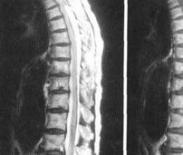

• 椎管內腫瘤

椎管內腫瘤,又稱為脊髓腫瘤,包括發生于脊髓本身及椎管內與脊髓臨近的各種組織(如神經根、硬脊膜、血管、脂肪組織、先天性胚胎殘余組織等)的原發性腫瘤或轉移性腫瘤的總稱...